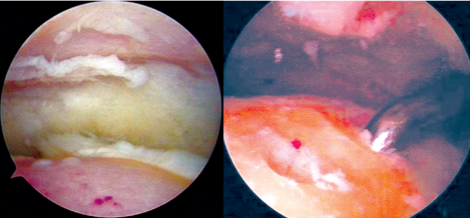

关节镜下见关节面软骨大面积缺损;关节镜下尖锥微骨折器处理关节面

关节镜下踝关节融合术是一种侵入性更小的手术,与开放手术相比,关节镜下融合术融合率更高、估计失血量更少、止血带时间更短、住院时间更短、患者接受度高、创伤小、术后恢复快、并发症少。在踝关节融合及距下关节融合中最常用的关节镜手术入路为外侧入路及后侧入路。

但是目前适应证包括创伤后关节炎、类风湿性关节炎、陈旧性剥脱性骨软骨炎、慢性踝关节不稳定、慢性踝关节感染、神经肌肉性关节疾病等,而且关节镜下踝关节融合术远期失败率和再次手术翻修率均高于其他手术方式。